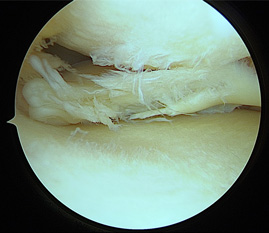

• 画像:損傷後内側半月板関節鏡画像

損傷後内側半月板関節鏡画像